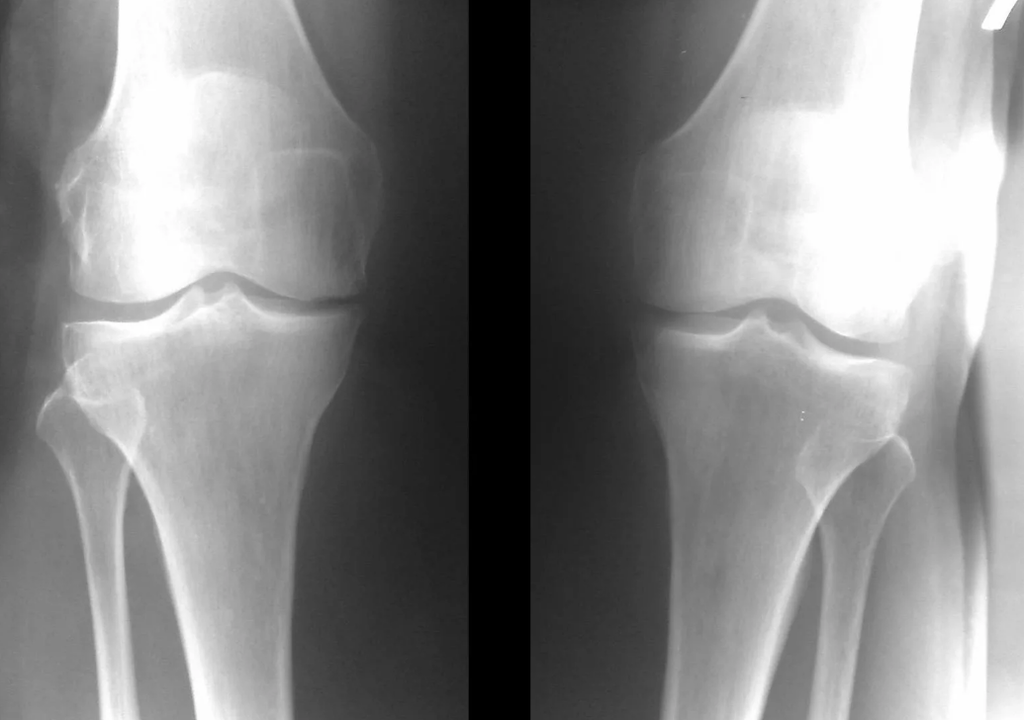

In the vast majority of cases, an examination and X-ray of the knee joint in two projections (direct and lateral) is sufficient.Clinical data and images help in determining the stage of the disease.

In the early stages of the disease, with minor changes in the bone tissue, the X-ray examination is not so valuable.At this stage, gonarthrosis can be diagnosed by arthroscopic examination.The precision of the method is very high;only its invasive nature and cost can stop it.

Ultrasound does not allow clear visualization of changes in articular cartilage and intra-articular structures.Using magnetic resonance, you can detect changes in the bones, cartilage and soft tissue structures of the joint, as well as the subchondral bone, with 85% accuracy.Scintigraphy can be used to assess the metabolic activity of periarticular bone tissue.